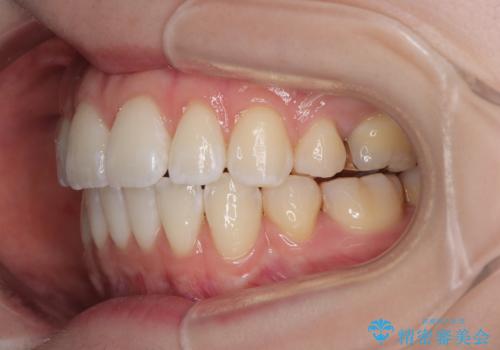

- くちばしのように飛び出した前歯を気にして来院された患者様です。

上下左右の第一小臼歯4本を抜歯して、ワイヤー装置にて矯正治療を行うこととしました。

舌の突出癖により、口元が突出しているだけでなく、上下前歯が非接触となっておりました。

舌のトレーニングをしっかりと行っていただくことで、2年を切って治療を終えるとともに

、上下前歯を接触させることができました。